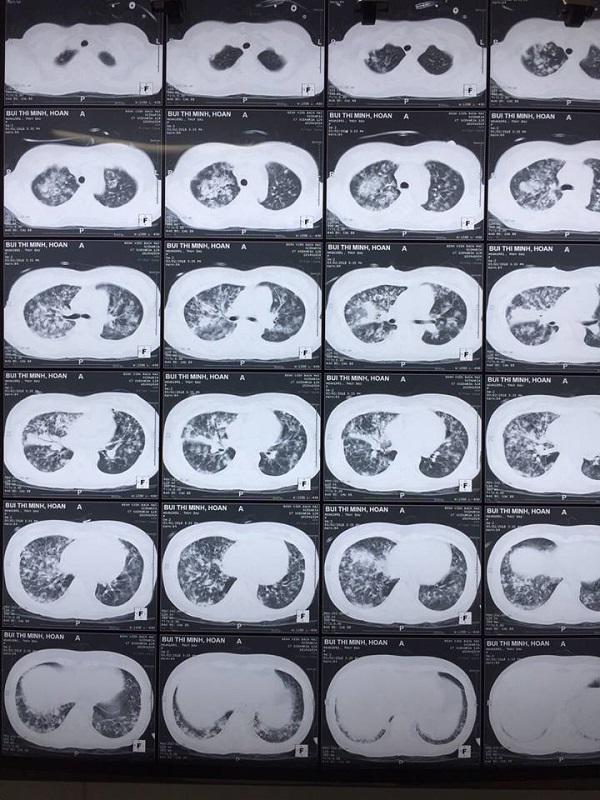

Hình ảnh chụp X-quang viêm phổi của bệnh nhân

Sau khi chuyển xuống khoa Truyền nhiễm 1 ngày, nữ bệnh nhân quê Tuyên Quang này khó thở, thở gắng sức, ho ít, thể trạng suy kiệt… Phim chụp XQ và các xét nghiệm cho thấy bệnh nhân bị biến chứng viêm phổi nặng sau thủy đậu, trên nền lupus ban đỏ hệ thống/hoại tử đầu chi.